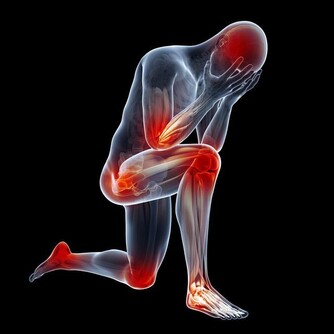

中醫認為,肝主藏血,肝臟每天會分解血液中的毒素或代謝產物,當肝臟受損時,其解毒能力也會有所下降,血液健康也可能受到一定影響。腳距離心臟較遠,如果腳掌紋路增多且變得明顯,要注意腳下保暖和保養肝髒了。